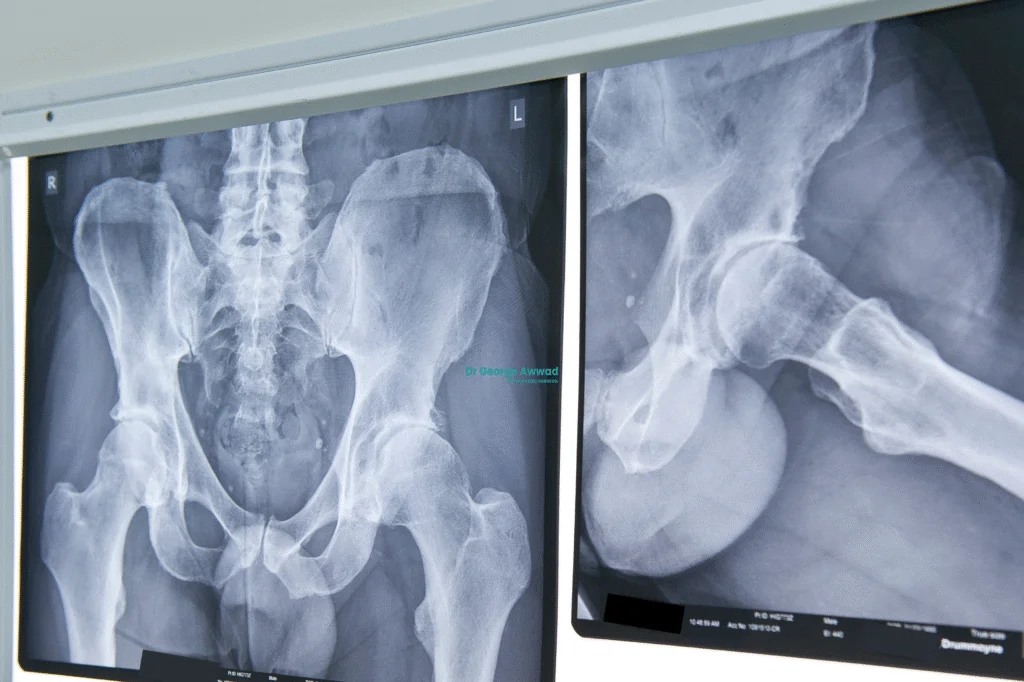

X-rays

Standard X-rays are the most commonly used imaging tool to detect hip arthritis. They can show joint space narrowing, bone spurs, cysts, or changes in the shape of the joint, all of which suggest degenerative or inflammatory changes. Different types of arthritis can produce distinct patterns on X-ray.